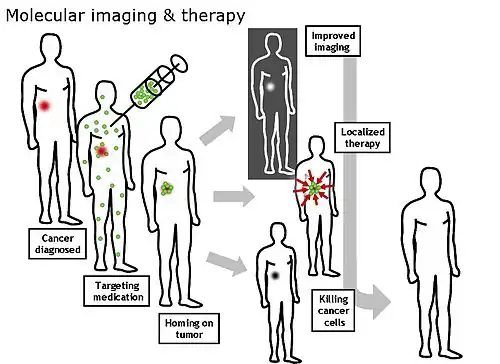

Molecular imaging is a field of medical imaging that focuses on imaging molecules of medical interest within living patients. This is in contrast to conventional methods for obtaining molecular information from preserved tissue samples, such as histology. Molecules of interest may be either ones produced naturally by the body, or synthetic molecules produced in a laboratory and injected into a patient by a doctor. The most common example of molecular imaging used clinically today is to inject a contrast agent (e.g., a microbubble, metal ion, or radioactive isotope) into a patient's bloodstream and to use an imaging modality (e.g., ultrasound, MRI, CT, PET) to track its movement in the body. Molecular imaging originated from the field of radiology from a need to better understand fundamental molecular processes inside organisms in a noninvasive manner.

The ultimate goal of molecular imaging is to be able to noninvasively monitor all of the biochemical processes occurring inside an organism in real time. Current research in molecular imaging involves cellular/molecular biology, chemistry, and medical physics, and is focused on: 1) developing imaging methods to detect previously undetectable types of molecules, 2) expanding the number and types of contrast agents available, and 3) developing functional contrast agents that provide information about the various activities that cells and tissues perform in both health and disease.

Molecular imaging emerged in the mid twentieth century as a discipline at the intersection of molecular biology and in vivo imaging. It enables the visualisation of the cellular function and the follow-up of the molecular process in living organisms without perturbing them. The multiple and numerous potentialities of this field are applicable to the diagnosis of diseases such as cancer, and neurological and cardiovascular diseases. This technique also contributes to improving the treatment of these disorders by optimizing the pre-clinical and clinical tests of new medication. They are also expected to have a major economic impact due to earlier and more precise diagnosis. Molecular and Functional Imaging has taken on a new direction since the description of the human genome. New paths in fundamental research, as well as in applied and industrial research, render the task of scientists more complex and increase the demands on them. Therefore, a tailor-made teaching program is in order.

Molecular imaging differs from traditional imaging in that probes known as biomarkers are used to help image particular targets or pathways. Biomarkers interact chemically with their surroundings and in turn alter the image according to molecular changes occurring within the area of interest. This process is markedly different from previous methods of imaging which primarily imaged differences in qualities such as density or water content. This ability to image fine molecular changes opens up an incredible number of exciting possibilities for medical application, including early detection and treatment of disease and basic pharmaceutical development. Furthermore, molecular imaging allows for quantitative tests, imparting a greater degree of objectivity to the study of these areas. One emerging technology is MALDI molecular imaging based on mass spectrometry.